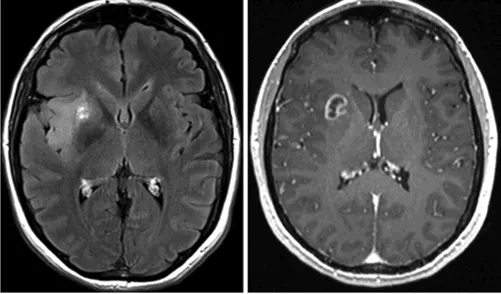

图2:2013年11月轴向FLAIR MR图像显示,肿瘤生长缓慢但客观可见。体积为11cm³。

术前评估:11cm³发展到21cm³,且出现恶化可能

然而,就在手术前一天的MRI检查中,发现肿瘤体积已急剧增长至21cm³——距离上次检查也才5个月。这一数据表明肿瘤进入了快速生长期,年增长率约13毫米,相比之前的1.8毫米/年——这样的进程高度符合高级别胶质瘤的发展特征。

“肿瘤可能已经发生恶性转化了(图3)。”

图3:术前即刻轴向FLAIR(左)和2014年4月轴向增强T1加权(右)磁共振图像显示肿瘤体积迅速增大(21cm³),在豆状核的前外侧部分突然出现“环状”对比增强。